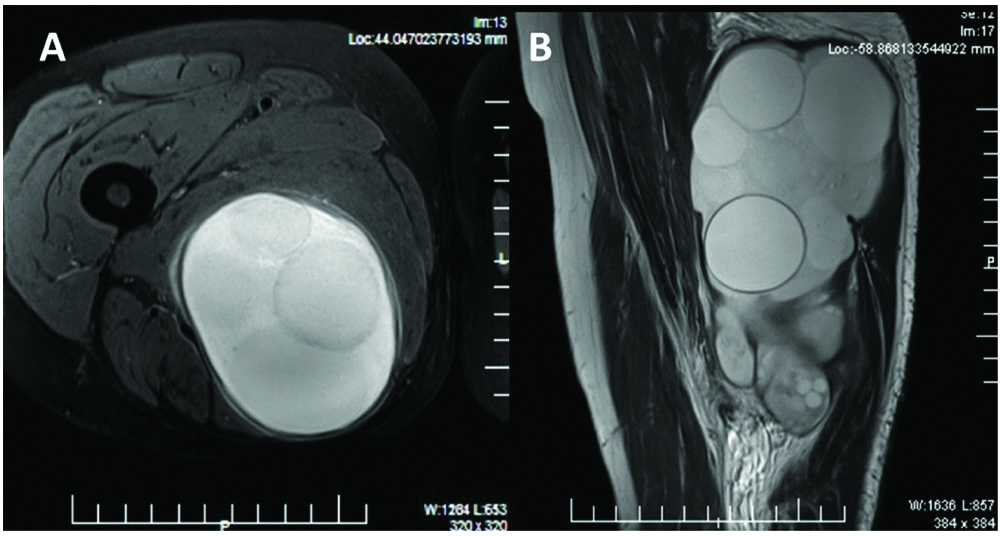

MRI revealed a 9.5×7.3×16.5 cm well-defined oval cystic lesion involving right adductor muscle at upper mid-thigh level with perifocal inflammatory oedema [Table/Fig-1]. Femur showed normal signal intensity. No abnormal medullary signal intensity was seen. No evidence of fracture, stress response or bone oedema was seen. Femoral neuro-vascular bundle and sciatic nerve appeared remarkable. The surgery was planned considering hydatid cyst as a provisional diagnosis.

(a) Transverse, (b) Longitudinal MRI section through the lesion.